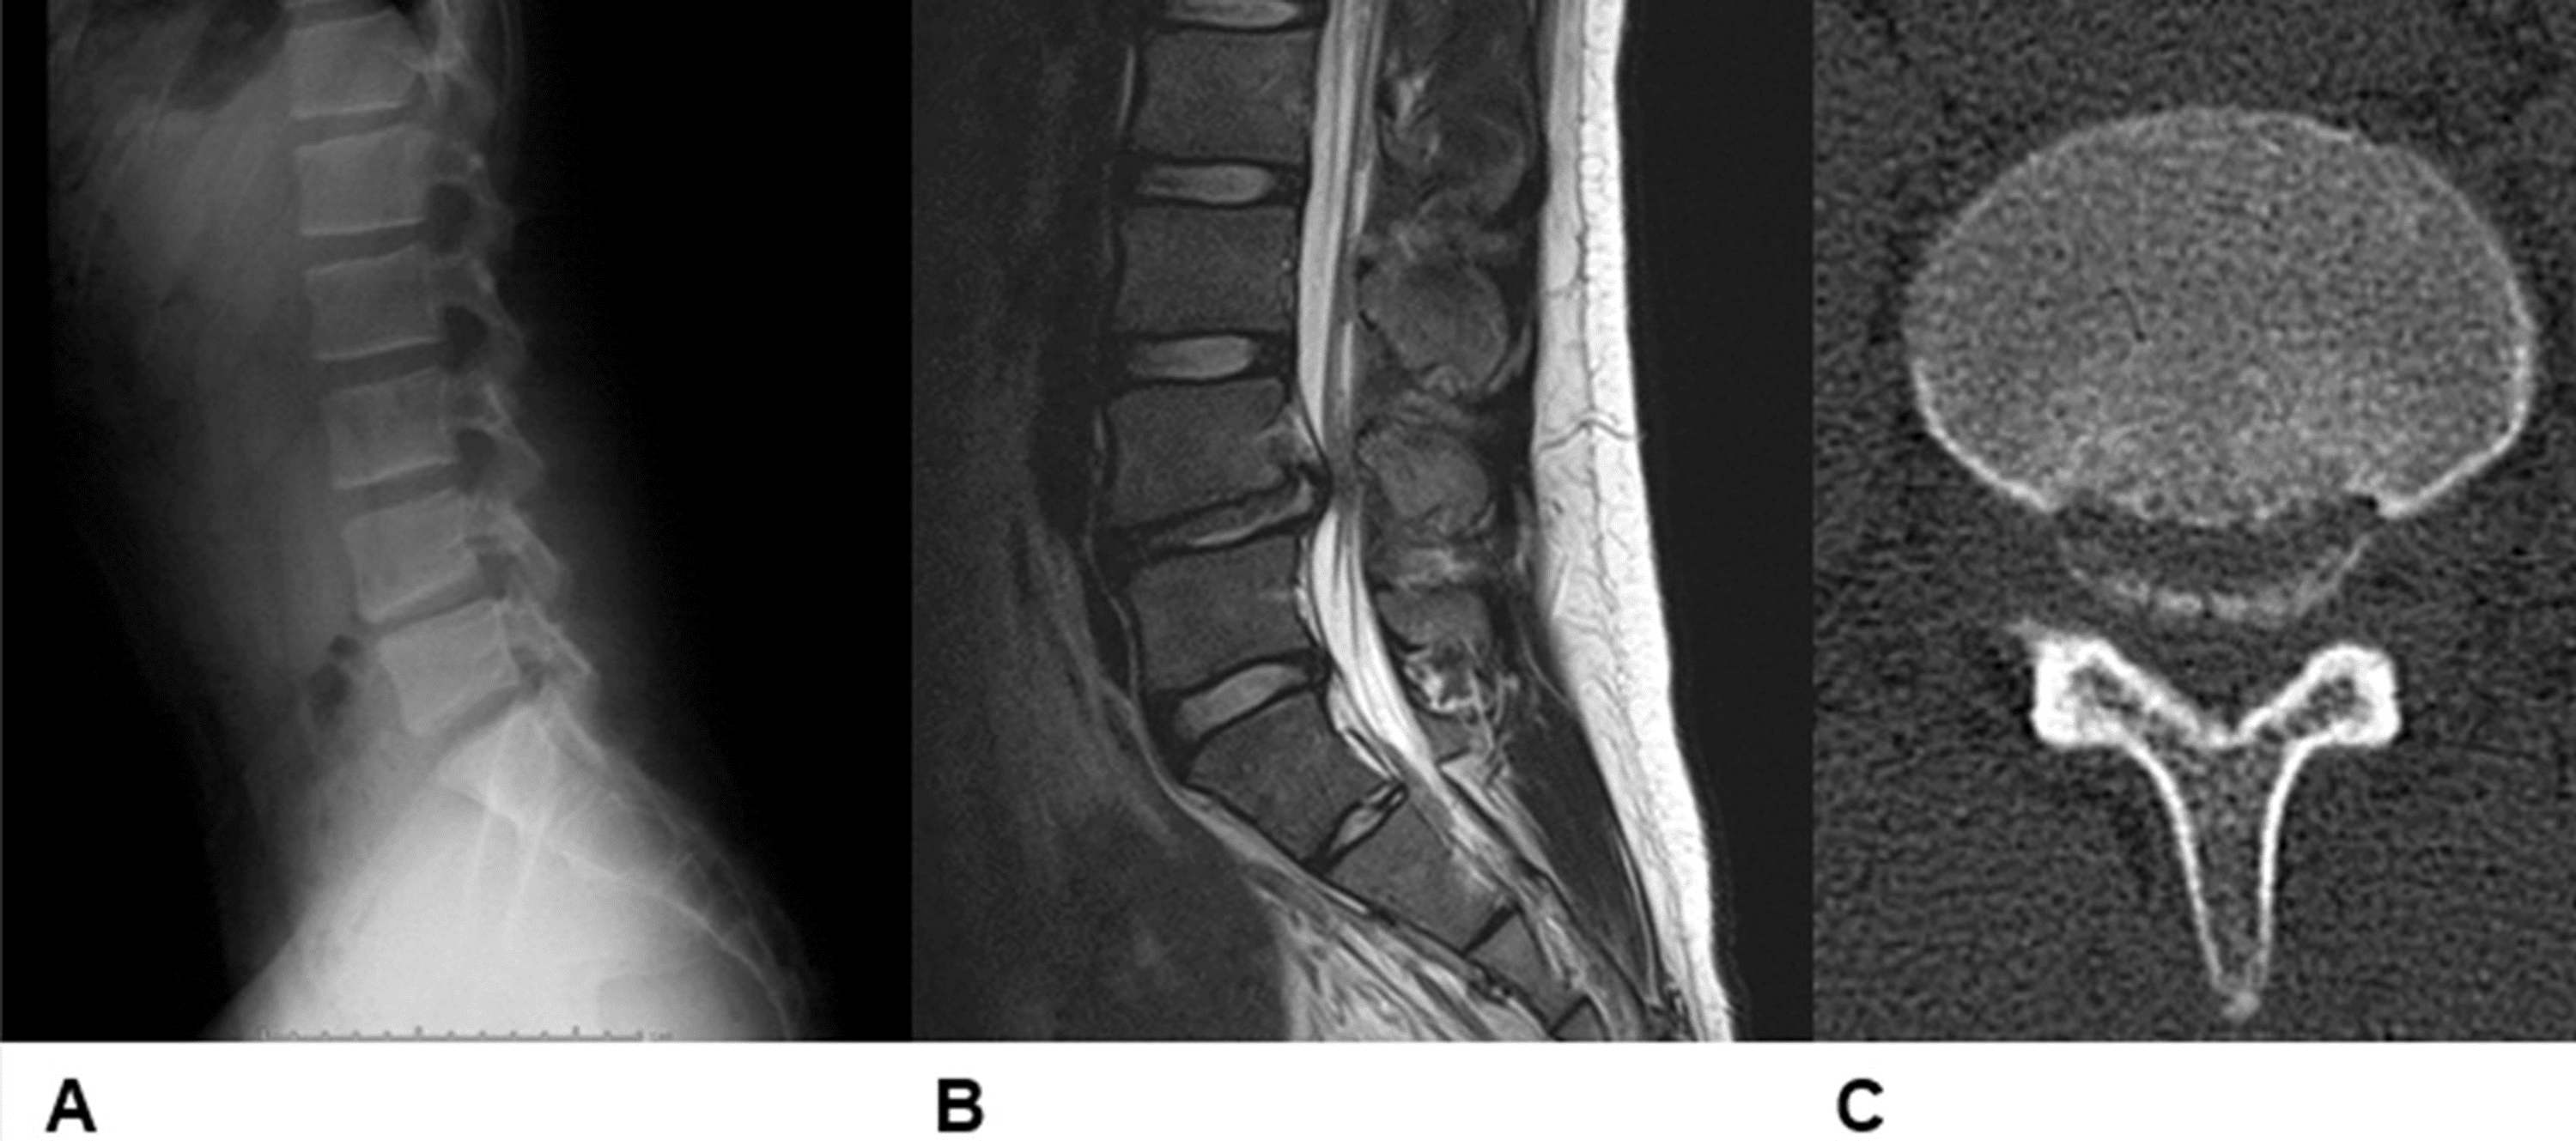

Male, 25 years old, L5/S1 lumbar disc herniation with posterior Ring Herniated Disk This pressure against the outer ring may cause lower back pain. It is a common cause of back pain. Herniated disc is a condition in which there is a lesion or rupture in the outer fibrous ring of the intervertebral disc (annulus), that leads to bulging of the inner portion. A herniated disk, which can occur in any part of.. Ring Herniated Disk.